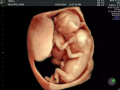

(图片来源网络,侵删)